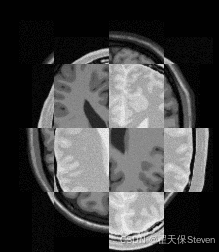

5. 可视化工具:棋盘图(CheckerBoard Image)

为直观对比配准效果,代码生成配准前后的棋盘图

• 原理:将固定图像与浮动图像按棋盘格模式交替拼接(如 2x2 像素块);

• 效果:配准前棋盘格明显错位,配准后棋盘格无缝对齐,可直接通过视觉判断配准精度。

配准前棋盘图

配准后棋盘图